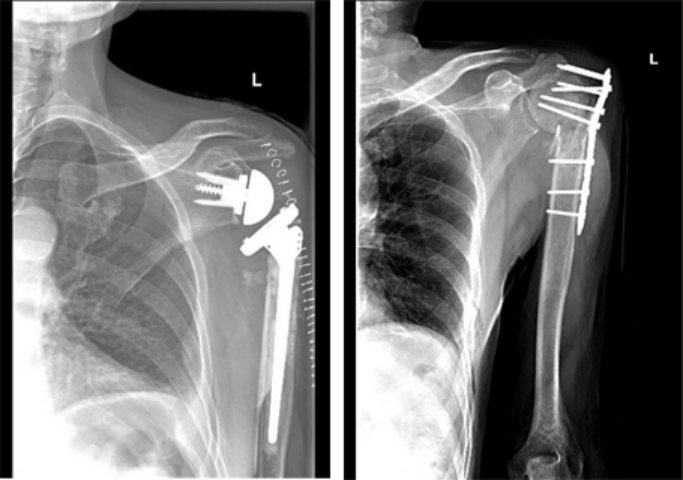

4.关节置换术

老年人关节内骨折合并骨质疏松症时,软骨下骨质量差,骨折块易嵌入关节面,解剖复位困难,骨折复位在下地负重或关节活动时难以维持,因此内固定治疗效果不佳。此时可酌情选择关节置换治疗,能够获得更好的预后。当骨折未累及关节面,但存在股骨头缺血性坏死风险时,例如股骨头下骨折或肱骨近端骨折,关节置换术的疗效优于内固定[27][28][29]。随着反肩关节置换术的出现,越来越多的骨科医生选择关节置换术治疗复杂的肱骨近端骨折,获得了良好的治疗效果;而肘关节置换术已经成为复杂骨质疏松性肱骨远端骨折的常规治疗手段,临床研究也验证了其优良且可靠的治疗效果[28]。因此,当骨质疏松性骨折骨质量差,骨折碎片较小时,人工关节置换术应首先考虑。